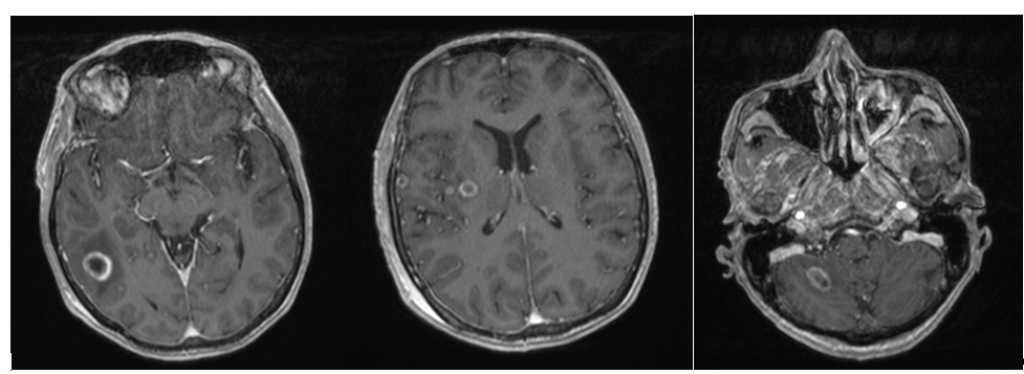

Ce premier Jeudi de l'oncologie de l'année donnera la parole à une équipe médicale pluridisciplinaire. Elle échangera avec vous sur les nouveaux modes de prise en charge des métastases cérébrales.

19:05  Indications opératoires des métastases cérébrales à l'ère des thérapies cibléesPr Evelyne EMERY et Dr Arthur LECLERC, CHU de Caen

19:25  Evolution de la prise en charge par radiothérapie des métastases cérébrales - Dr Dinu STEFAN, CFB Caen

19:40  Prise en charge oncologique des métastases cérébrales à l'ère des thérapies ciblées dans les cancers du sein Dr Ioana HRAB, du poumon Dr Radj GERVAIS et les mélanomes, Dr Margaux MORDREL, CFB Caen